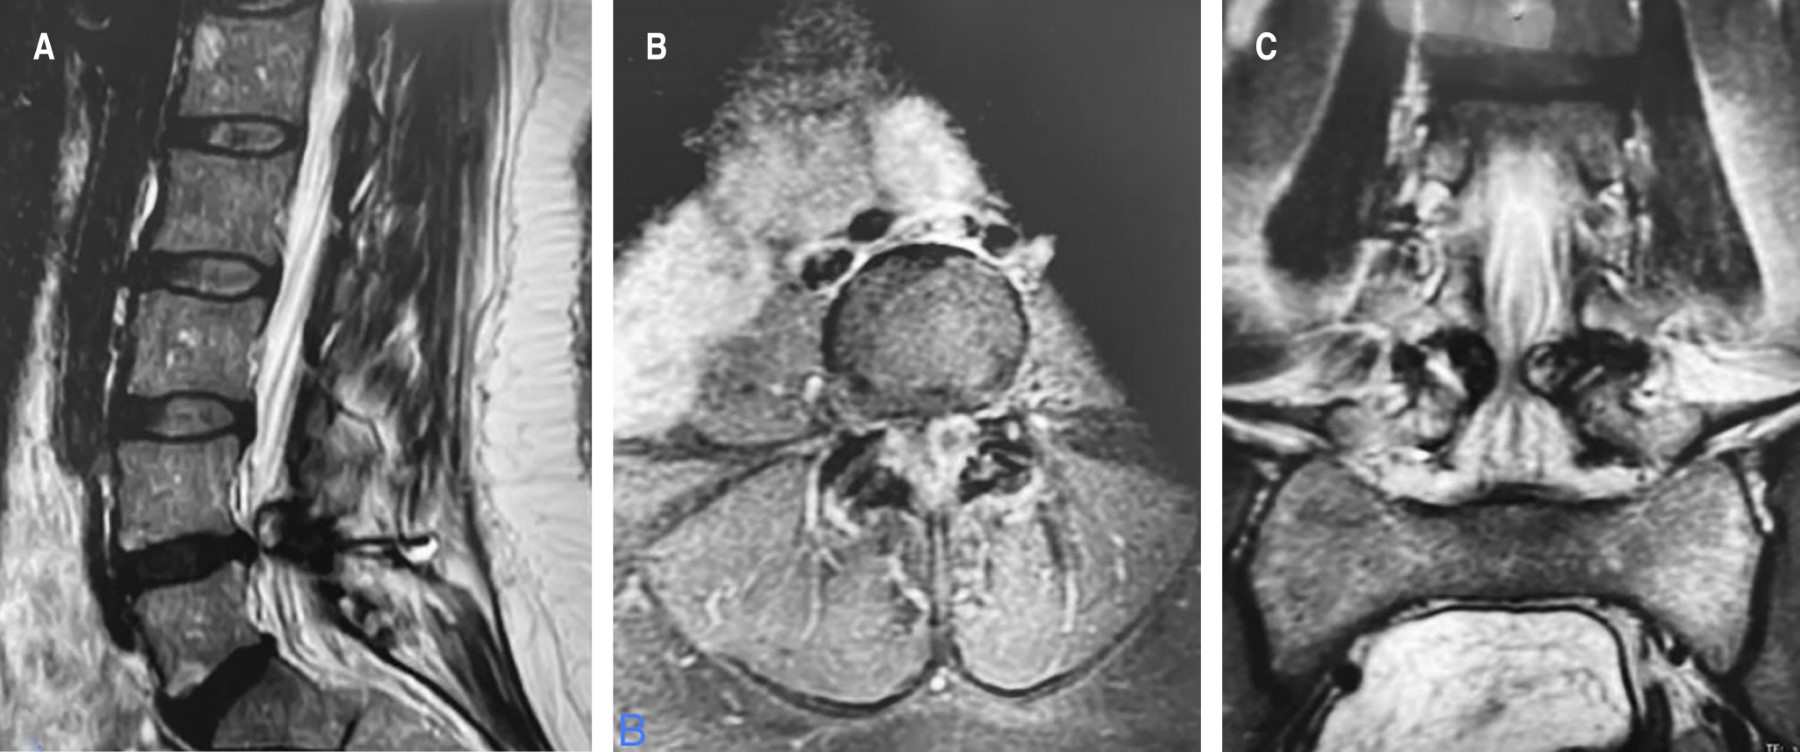

Calcification of the ligamentum flavum is a rare disease that affects mainly elderly women. This calcification is a rare condition in the lumbar spine, different studies conclude that it is more likely to occur in the lower thoracic spine in the first place and in the cervical spine in the second place. The mechanisms of ligament calcification in the lumbar spine are associated with high mechanical stress in this segment, it has been demonstrated that humoral and genetic factors also play an important role for ligament calcification, this suggests that ligamentum flavum calcification is related to alterations in bone metabolism associated with intrinsic factors such as mechanical factors. There are few cases reported in the literature of radicular presentation associated with calcification of the ligamentum flavum in the lumbar spine. In young patients, it may clinically manifest as lumbar myeloradiculopathy. The cauda equina syndrome resulting from compression of the nerve roots consists of lumbar pain, uni or bilateral radicular pain, sensory disorders and alterations in the sexual and/or sphincteric sphere. The most common cause of this syndrome is an extruded disc herniation; however, any lesion that causes compression of the nerve roots distal to the conus medullaris, whether due to tumors, trauma, calcification or ossification of ligament structures and post-surgical complications will result in cauda equina syndrome. We present the case of a 35-year-old female patient with calcification of the ligamentum flavum in the lumbar spine presenting radiculopathy, alterations in sensibility and urinary incontinence. Magnetic resonance imaging showed compression of the cauda equina at L4-L5 on the left side. Decompressive laminectomy of L4 and L5 with resection of the calcified ligamentum flavum was performed. Histopathological findings showed acellular hyaline changes and dystrophic calcifications of the ligamentum flavum. Alterations in sensation and urinary incontinence improved after surgery. The understanding of the external factors, the pathogenesis and the clinical presentation supported by imaging studies guide us to the diagnosis of this rare condition.

Figure 1